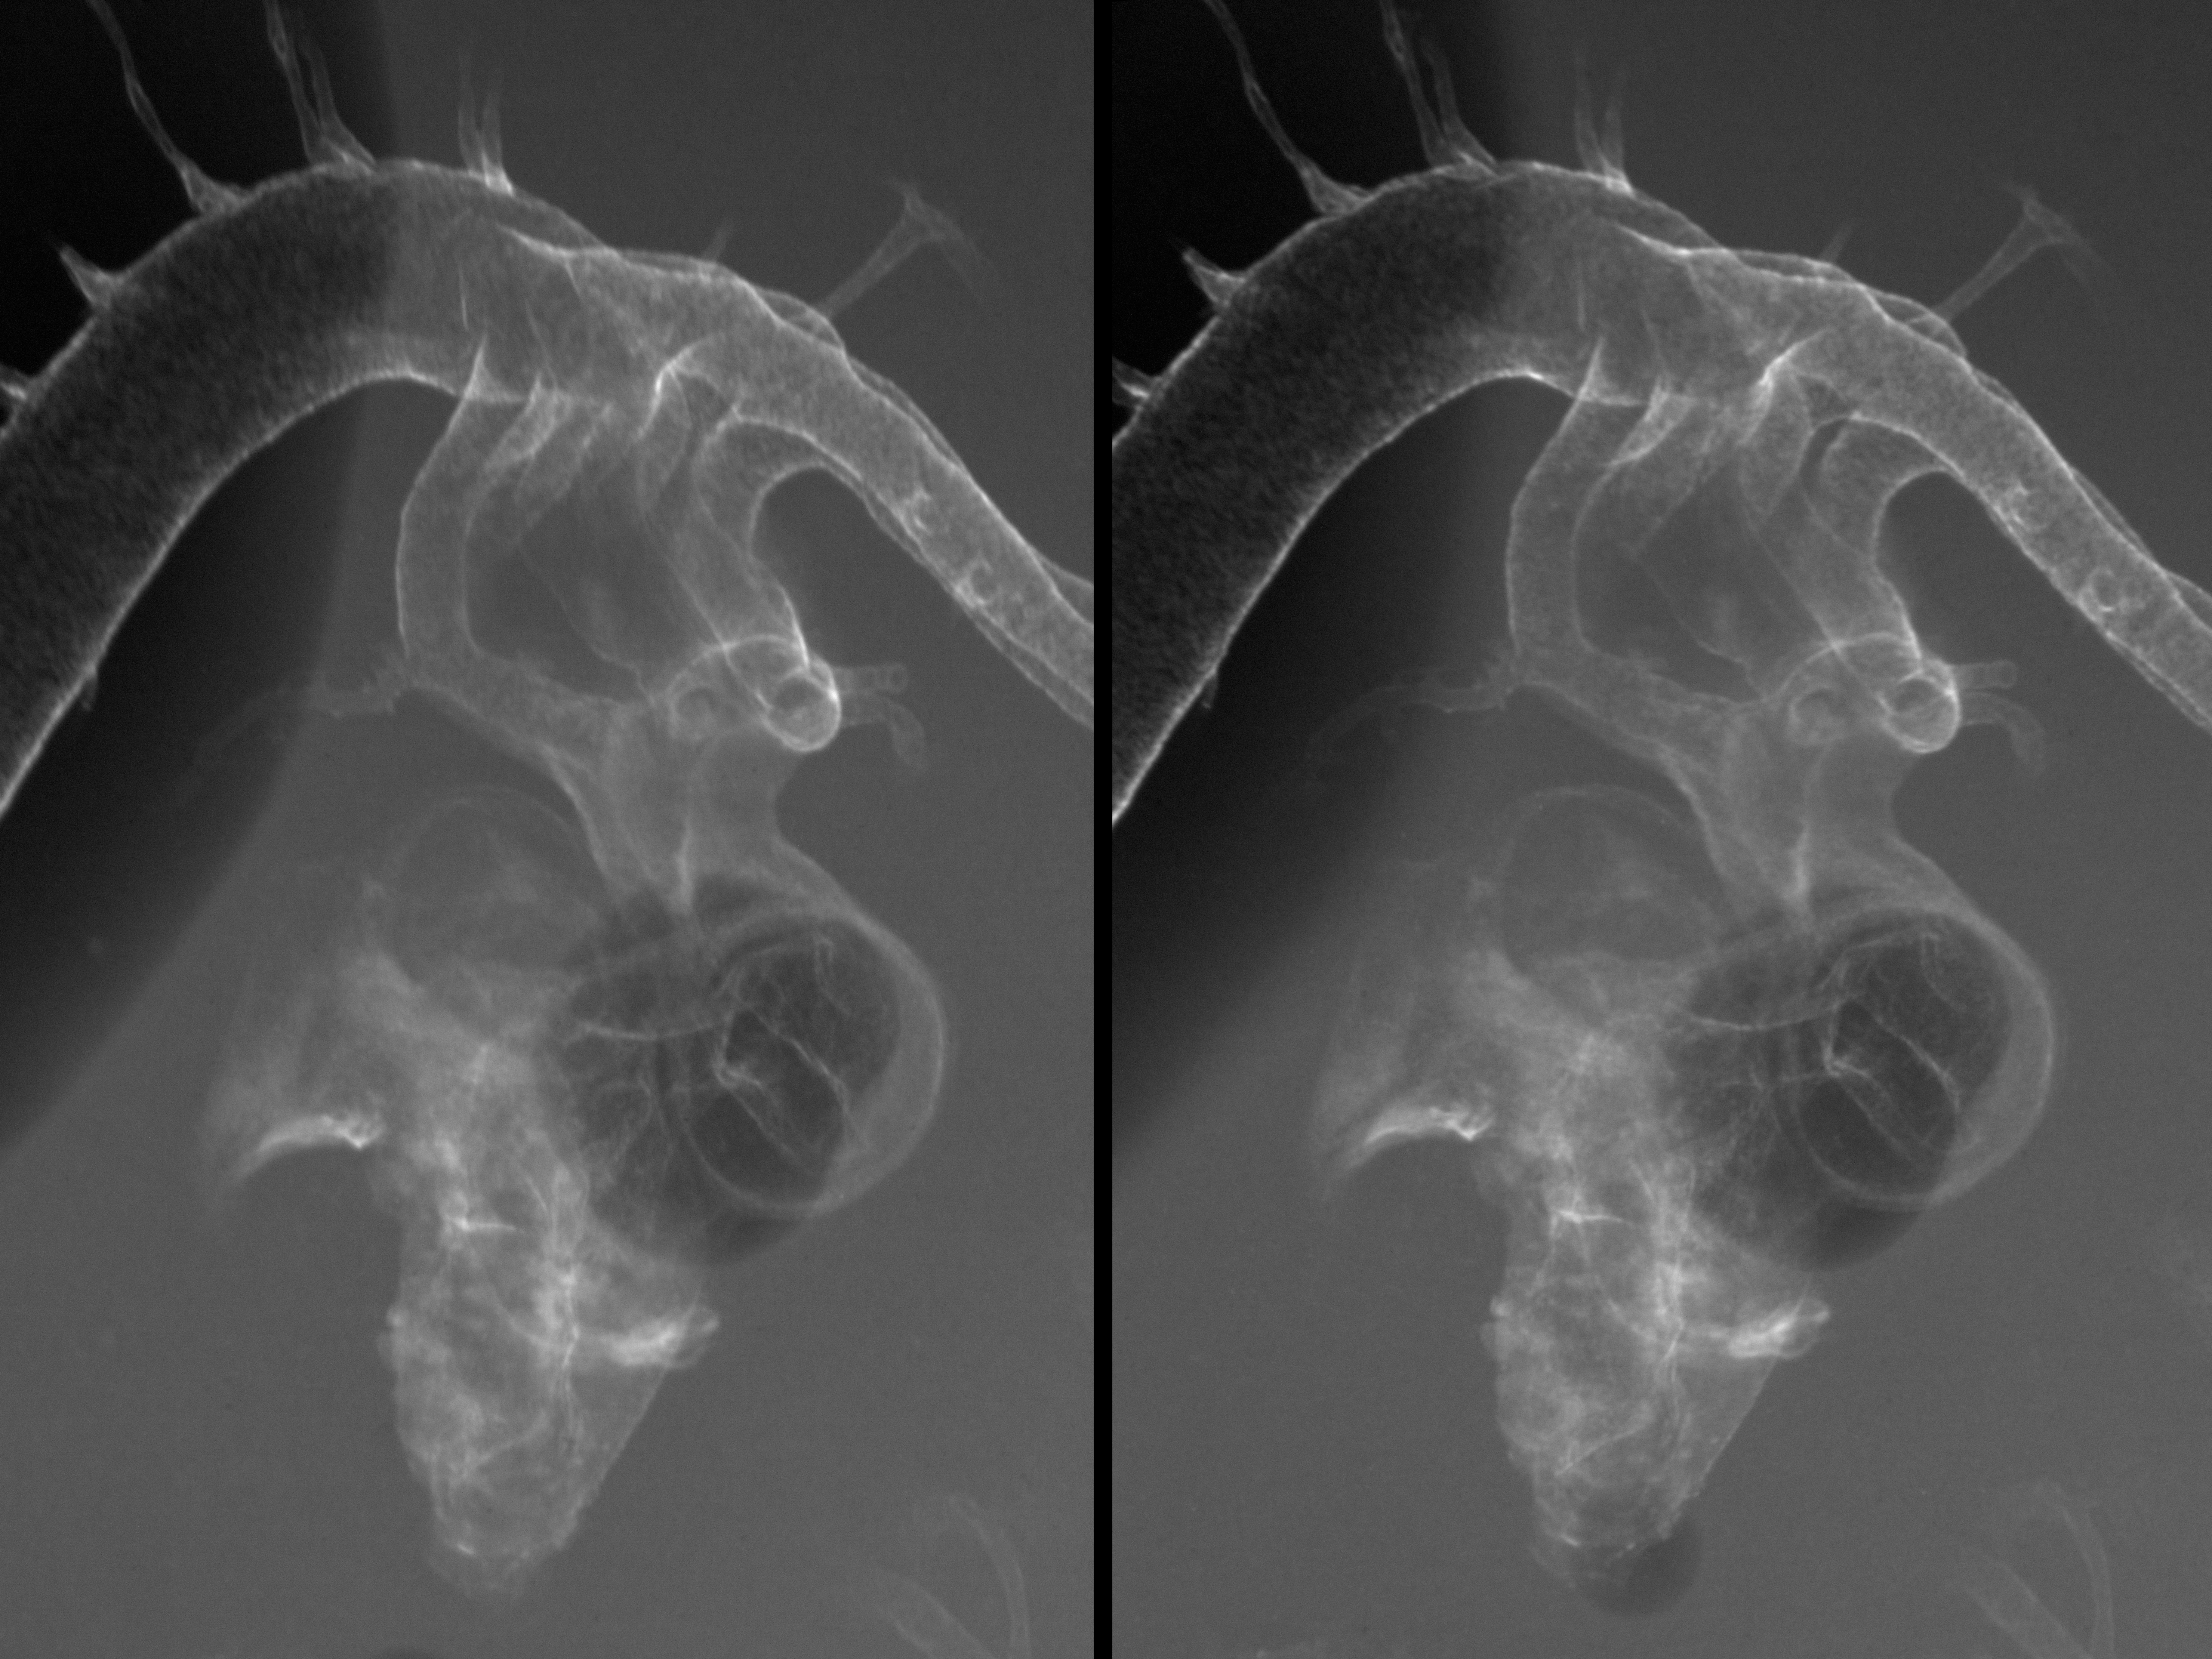

Chick Embryo Microangiography

Hamburger-Hamilton (HH) Stage 23 (approx. 4 days)

Stereo X-Ray Micrographs